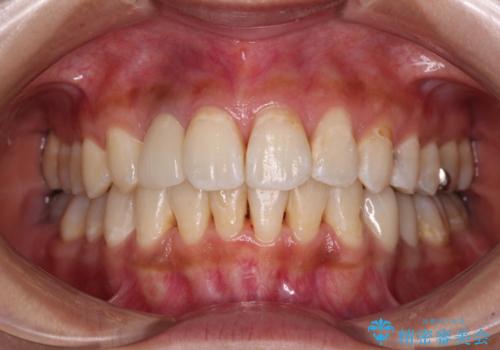

デコボコで磨きにくい前歯をスッキリと インビザライン矯正

神経が取り除かれている歯は、クラウンによる補綴治療が必要であるため、矯正治療後にオールセラミッククラウンにて補綴治療を行うこととしました。

歯磨きしやすくなるとともに、飛び出していた前歯も引っ込めて整えることができました。